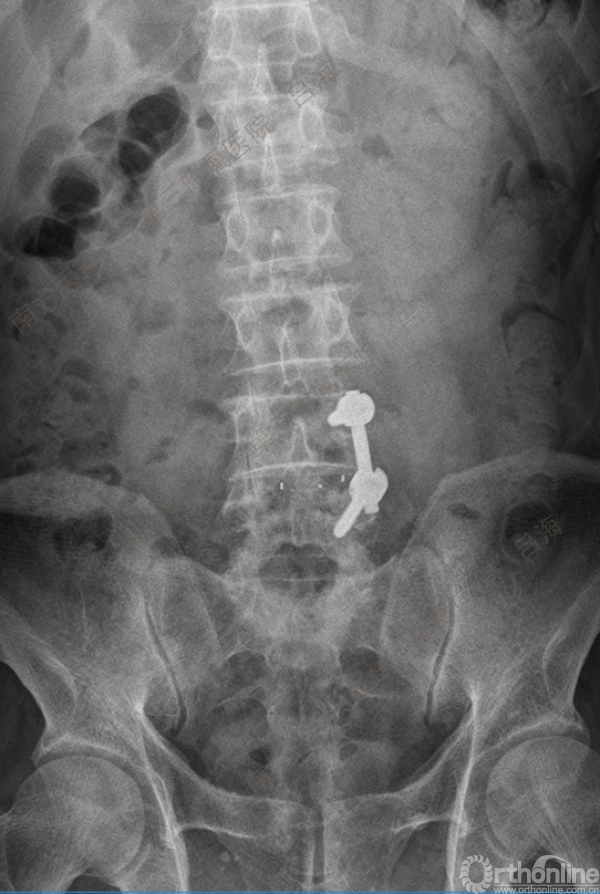

随着社会老龄化进程加快,胸腰椎退行性病变的治疗已经成为脊柱学术界的一个热点话题。MIS-TLIF手术可以治疗多种不同的胸腰椎退行性疾病,南方医科大学第三附属医院吕海教授结合病例为我们一一展示了该术式在治疗不同胸腰椎疾病时的具体手术过程。